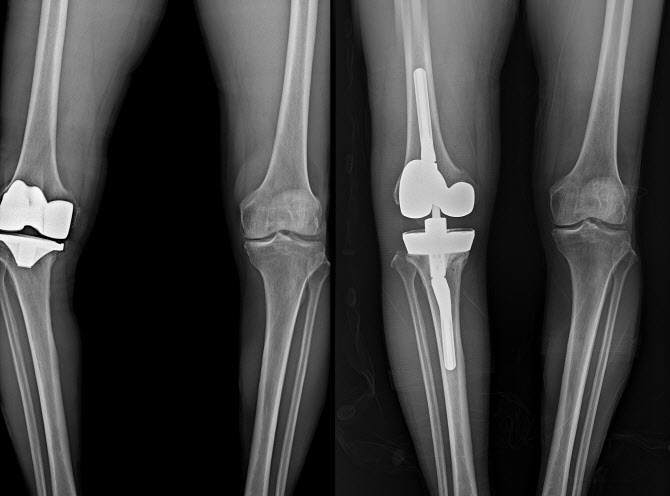

무릎 인공관절 재수술 전(좌)과 후.